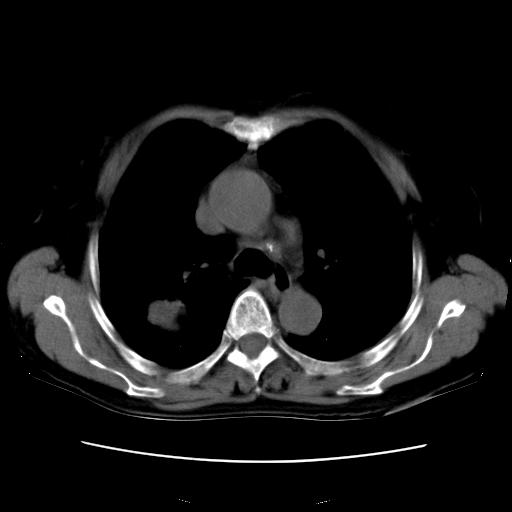

以下是引用卜一在2007-9-18 14:41:00的发言:[br]右肺肿块:毛刺+胸膜凹陷征+供血血管+浅分叶+强化。支持:周围性肺癌 !另:左侧甲状腺腺瘤!

以下是引用夏季在2007-9-18 11:00:00的发言:[br]1。右肺肿块,周围有短毛刺,肺门侧有血管与其相连,胸壁侧有胸膜凹陷征,考虑周围性肺癌 2。左侧甲状腺软组织肿块,内有高密度钙化灶,考虑左侧甲状腺腺瘤。